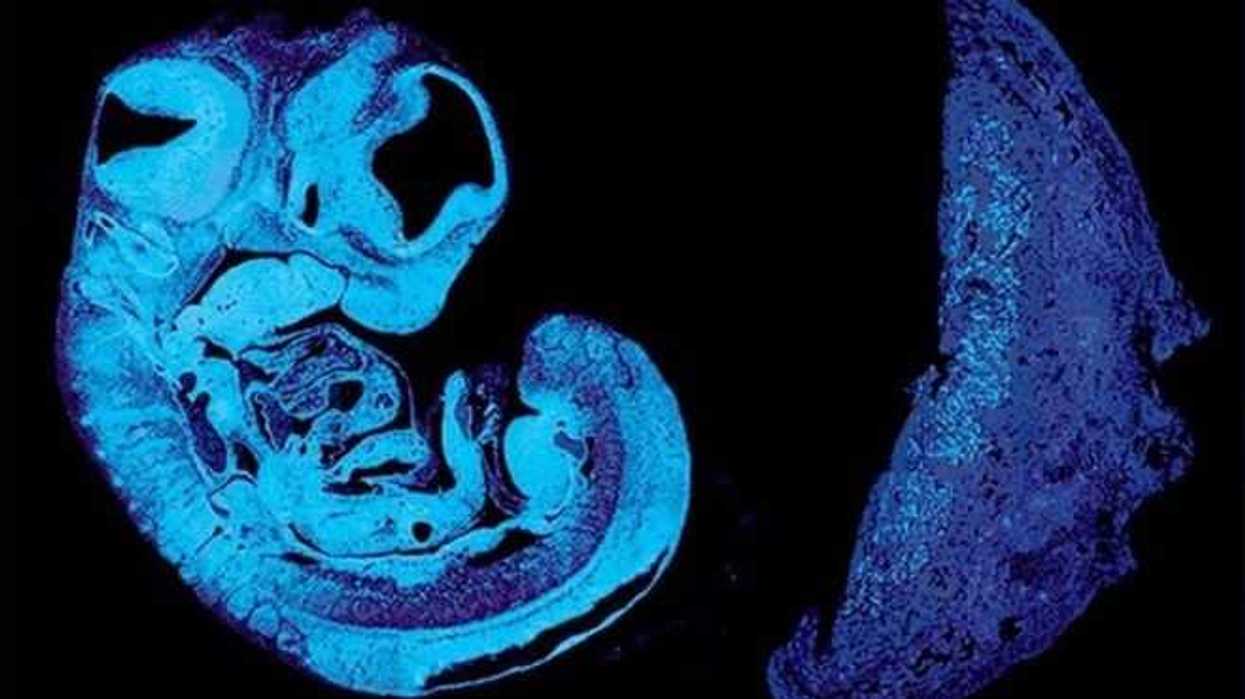

Los científicos usaron ratones modificados genéticamente para mostrar cómo el feto produce esa señal que fomenta el crecimiento de los vasos sanguíneos dentro de la placenta, que provoca también modificaciones en otras células para permitir que le lleguen más nutrientes.

En los ratones, la respuesta al IGF2 en los vasos sanguíneos de la placenta está mediada por otra proteína, denominada IGF2R. Los dos genes que producen el IGF2 y el IGF2R están "impresos", un proceso por el que los interruptores moleculares de los genes identifican su origen paterno y pueden activar o desactivar los genes.